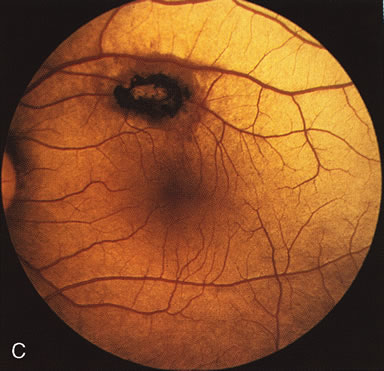

Fig. 2. Golden tapetal reflexes. There are three diseases in which there is an unusual golden reflex to the fundus: X-linked recessive RP in the carrier female, Oguchi's disease, and cone dystrophy. In all these diseases the angiogram is essentially normal, suggesting that this reflex is probably not related to pigment abnormalities. A, B. Carrier female of XLR retinitis pigmentosa. A golden scintillating reflex radiates from the macula. C, D. Oguchi's disease. A diffuse yellow metallic sheen is seen in the posterior pole (a pigmented chorioretinal lesion is an incidental finding). E, F. Progressive cone dystrophy. The typical bull's eye maculopathy is associated with a golden orange reflex.

In Oguchi's disease the hallmark fundus finding is a yellow metallic sheen (Fig. 2C). A similar sheen has been seen in progressive cone dystrophies and juvenile macular degeneration.7 In all these diseases the abnormal reflex does not affect the normal transmission of fluorescein dye (Fig. 2D). The normal FA suggests that, like findings in the carrier female in XLR RP, the abnormal retinal reflex in this disease is unrelated to pigment concentration or distribution.